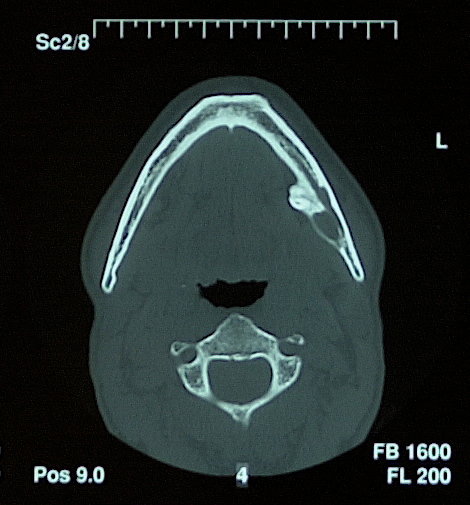

3D Röntgenbild